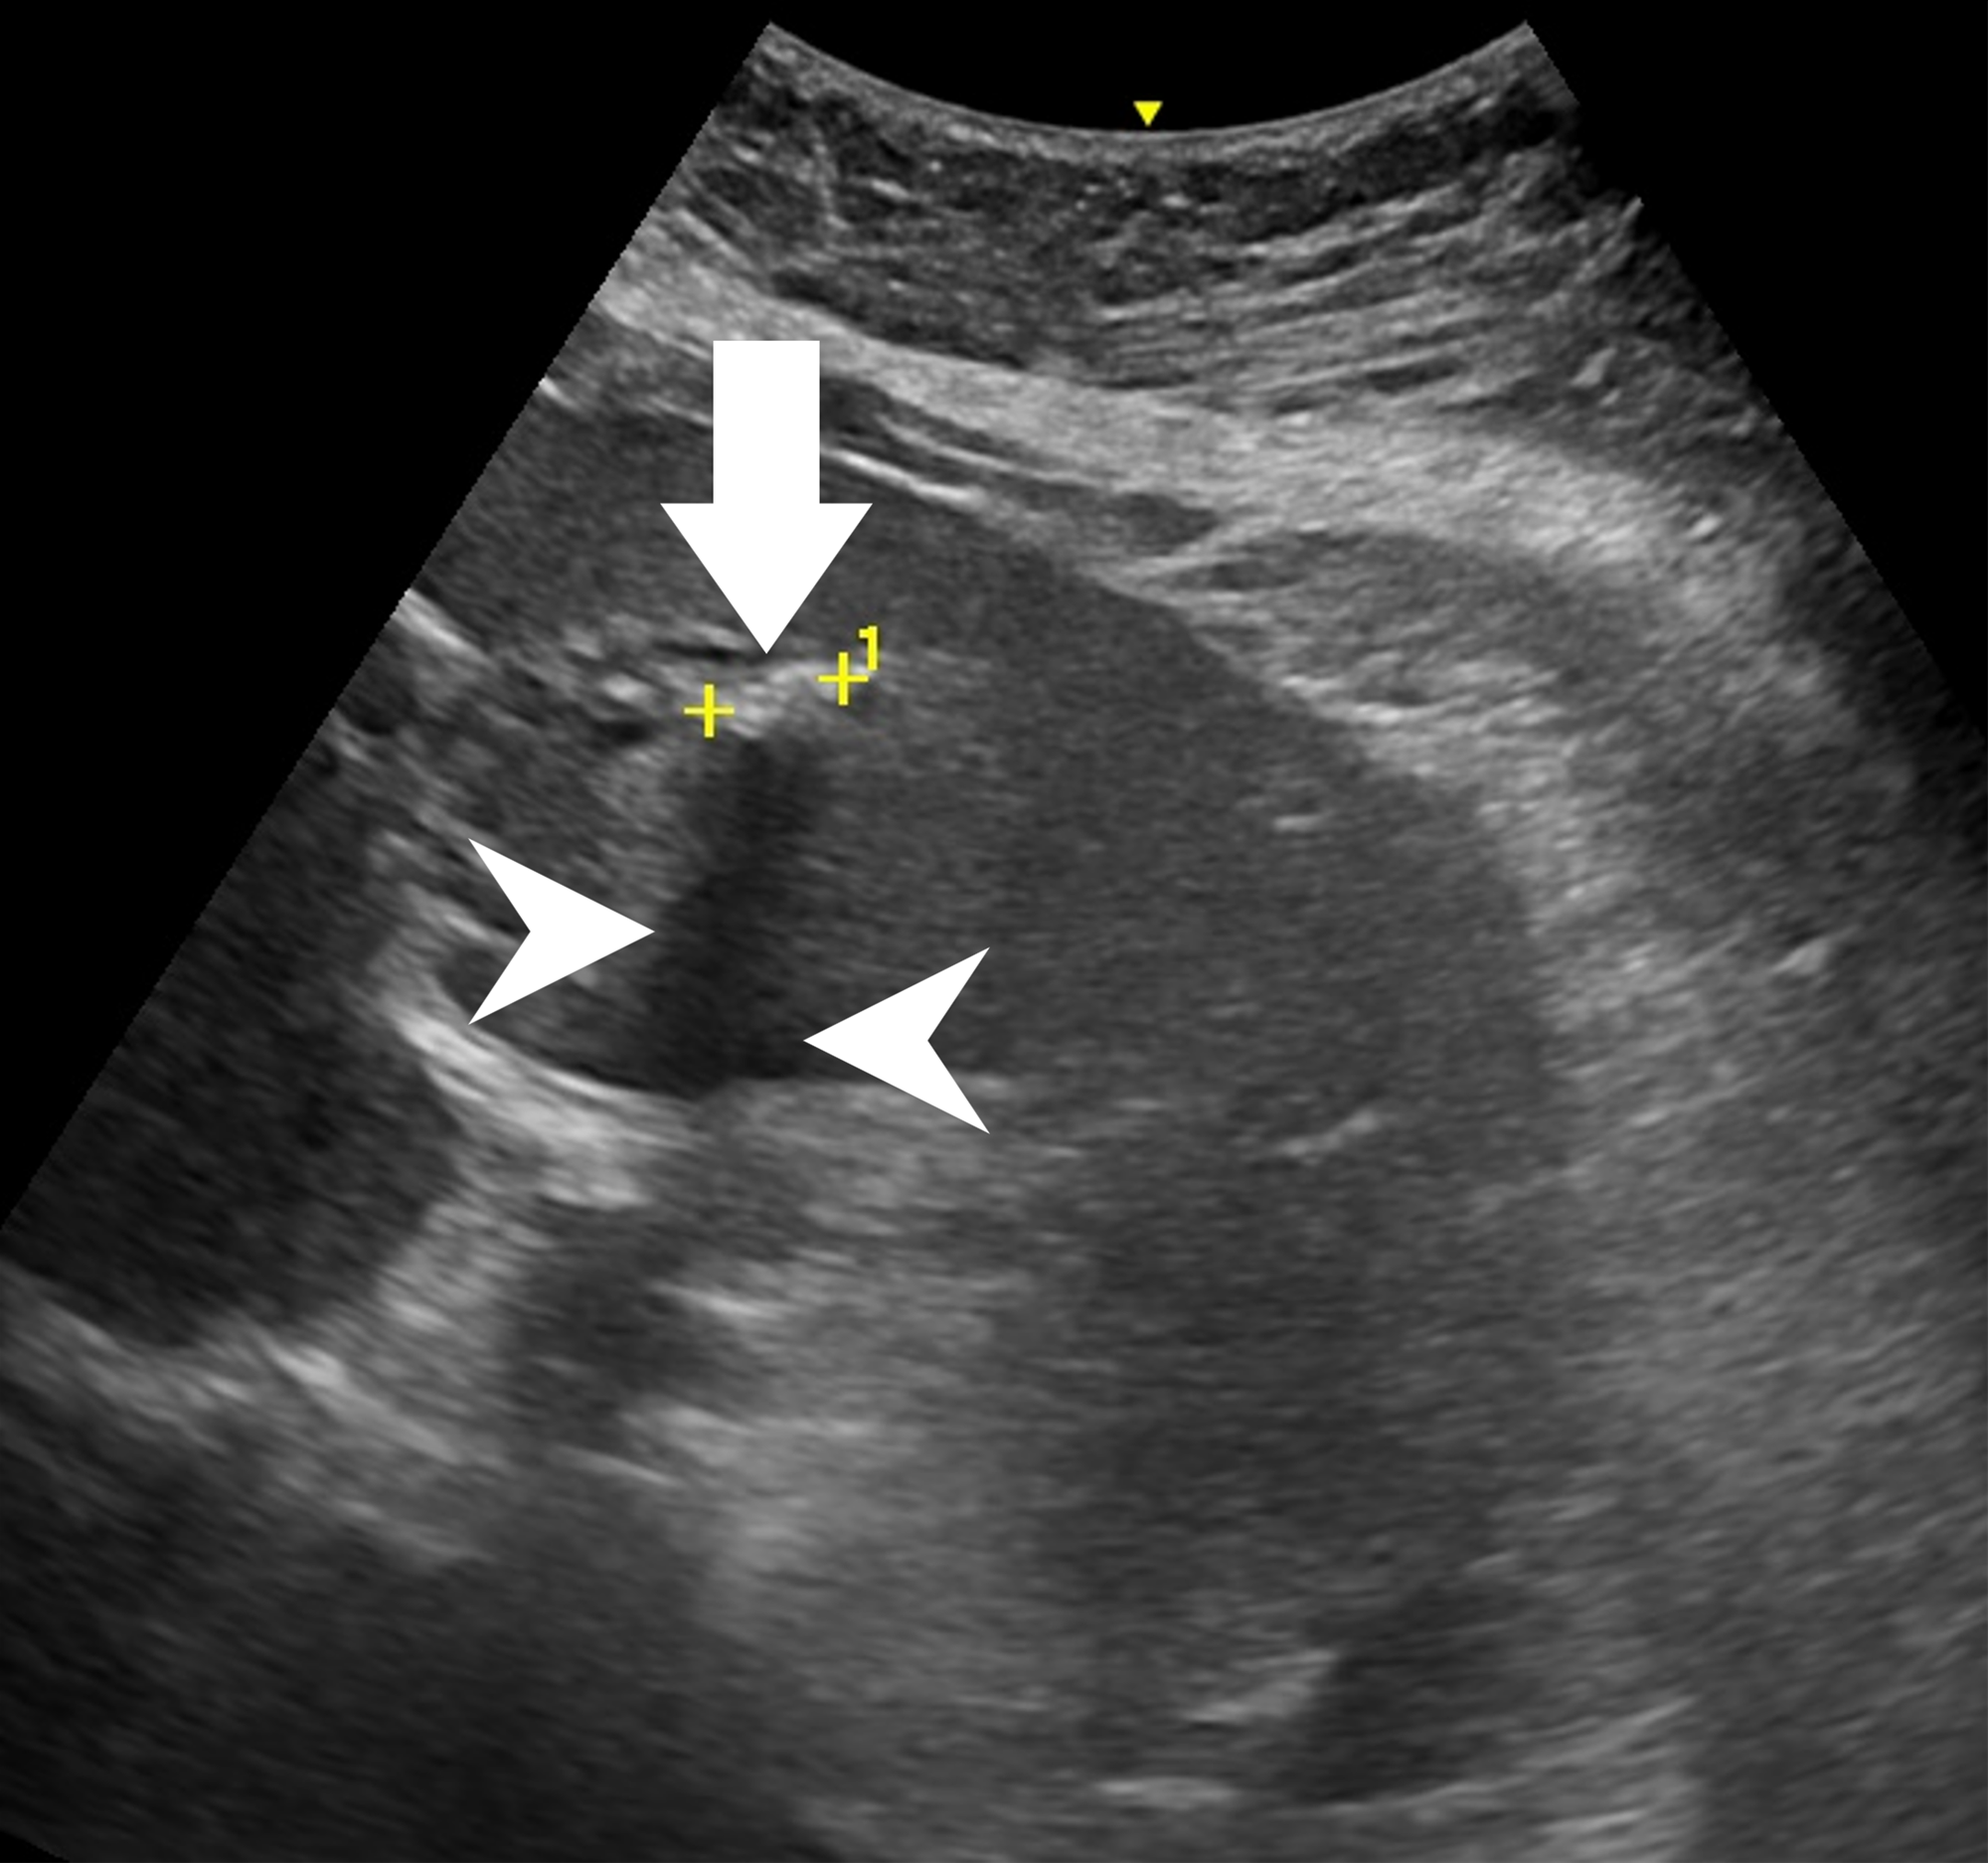

59歲陳女士長期承受間歇性腹痛,九月間於外院住院治療仍無改善,出院後轉至臺中市立老人復健綜合醫院。於肝膽腸胃科由內科部部長賴學洲醫師安排腹部超音波及核磁共振檢查,確診為左側肝內結石合併慢性肝內膽管炎及膽囊細沙併慢性膽囊炎,後經一般外科主任曹連誠醫師評估,安排 3D 立體內視鏡左肝切除加膽囊切除手術。患者術後恢復良好,第二天即可下床行走,自理生活,成功擺脫惱人的腹痛與長年不適。

圖說一、腹部超音波顯示左肝內膽管結石及結石造成的陰影。